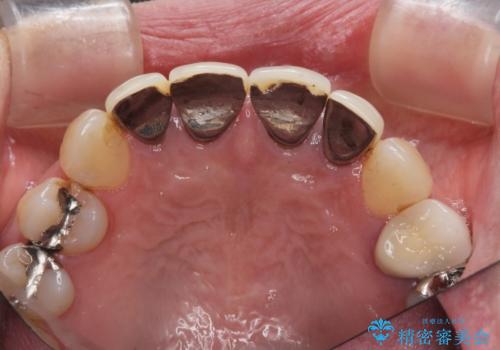

- 「黒ずみの前立つ前歯をやりかえ、きれいにしたい。」と希望され来院されました。

金属色の目立つ前装冠を除去し、発生していた小さな虫歯を丁寧に全て除去しジルコニアセラミッククラウンで審美的な前歯となるような治療を計画します。